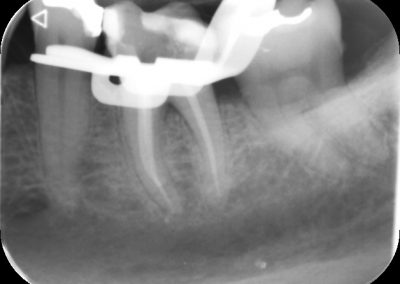

Before commencing the treatment, a local anaesthetic is administered and later a protective non-latex rubber sheet is placed around the tooth to prevent saliva contaminating the tooth and at the same time improves patients comfort.

An access cavity is placed on the surface where the patient bites, to reach the root canals of the tooth. Once all the canals are identified, small files are used to remove the infected pulp.

Files of different sizes are used to eliminate bacteria and infection and to shape the canals. The canals are disinfected thoroughly with irrigants and later the canals will be sealed in 3 dimensions with a special medicament called gutta-percha to prevent reinfection of the tooth and the access cavity will be sealed with a temporary filling.